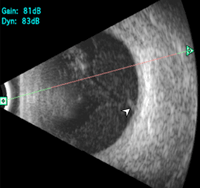

Desprendimiento de retina

Aparece como una membrana continua, de espesor regular y brillante, que puede adquirir diferentes formas (bulloso, plano, en embudo), seguida por un espacio anecogénico (

Figura 10). En modo A, el pico de reflectancia es del 100%, excepto en retinas atróficas o con abundantes pliegues.

Figura 10. Desprendimiento de retina con adherencia al nervio óptico.